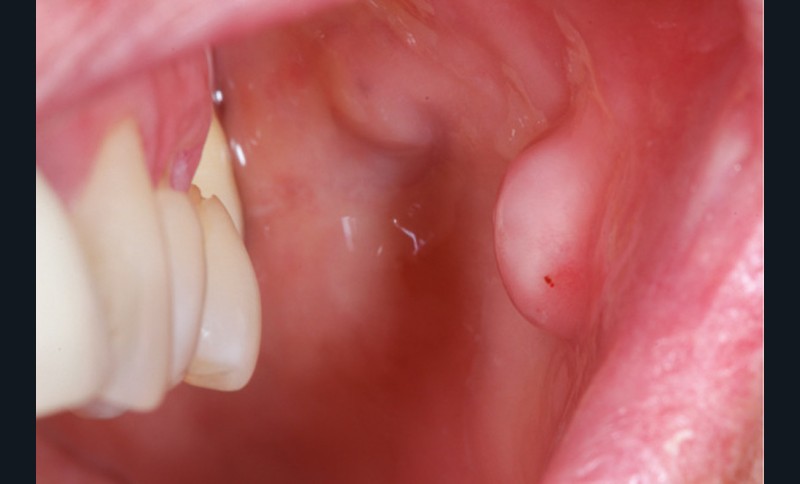

Conséquences muqueuses [11, 12]

Une extraction non compensée entraîne une vacuité de l’arcade par laquelle la muqueuse peut être « aspirée ». Il en résulte une excroissance de la joue ou de la lèvre par exemple, de forme sphérique le plus souvent. Il s’agit d’une tumeur bénigne correspondant à une hyperplasie fibro-épithéliale. Cette hyperplasie peut être retirée, mais il y aura récidive jusqu’au rétablissement de la continuité de l’arcade. Cela peut être gênant esthétiquement, mais peut aussi être à l’origine de morsures lors de la phonation ou de la mastication (fig. 20 et 21).